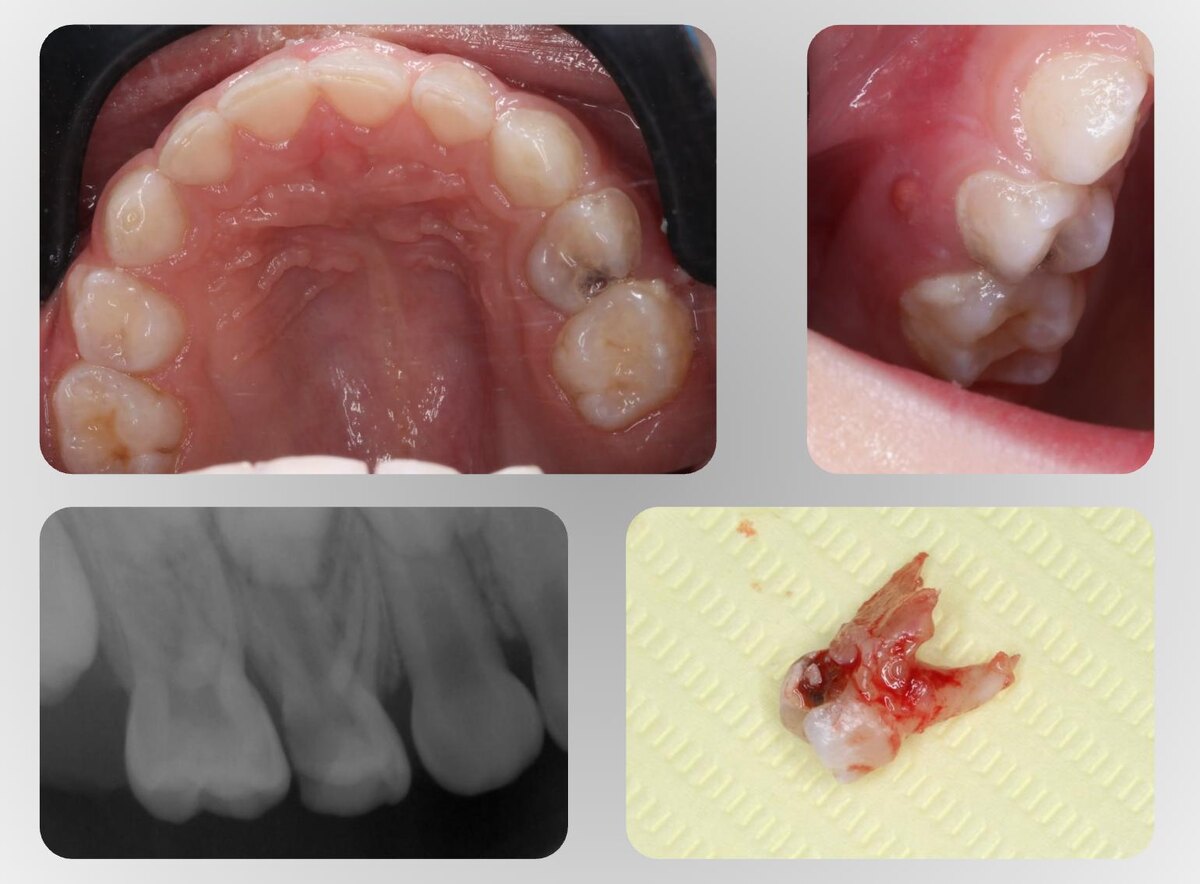

Как понять, что зуб действительно нужно удалять. Кейс.

Кейс из практики. Речь про молочный зуб — 54. Пациенты уже были в нескольких клиниках. В одной сказали: «удалять». В другой — хирург, к которому пришли уже на удаление, отправил искать возможность лечения: «зуб можно сохранить». Родители пришли за третьим мнением к нам. На этапе сбора анамнеза мама говорит: «Знаете, у него на десне появилась шишка». Это 👉 свищ. Свищевой ход — показатель для врача, что в зубе не просто кариес, а если зуб еще и болит, то это точно периодонтит. Дальше диагностика. Мы сделали снимок, и он подтвердил мои догадки: • периапикальные изменения, • большой очаг разрушения костной ткани, • признаки резорбции корней. ❗️В такой ситуации выбор, к сожалению, один — удаление. Потому что лечение либо сохранение зуба будет неуспешным, это приведет к осложнениям для зачатка постоянного зуба 1.4. А для нас приоритет — безопасность и сохранение постоянного зуба. После удаления жевательного зуба в возрасте 5 лет — ребенка обязательно направлять к ортодонту. Родителям я подр

Свищевой ход — показатель для врача, что в зубе не просто кариес, а если зуб еще и болит, то это точно периодонтит. Дальше диагностика. Мы сделали снимок, и он подтвердил мои догадки:

• периапикальные изменения,

• большой очаг разрушения костной ткани,

• признаки резорбции корней.

❗️В такой ситуации выбор, к сожалению, один — удаление.

Потому что лечение либо сохранение зуба будет неуспешным, это приведет к осложнениям для зачатка постоянного зуба 1.4. А для нас приоритет безопасность и сохранение постоянного зуба. После удаления жевательного зуба в возрасте 5 лет — ребенка обязательно направлять к ортодонту.

Родителям я подробно всё показала: diagnocat, снимки, фото, объяснила логику решения, привела аргументы и они согласились.